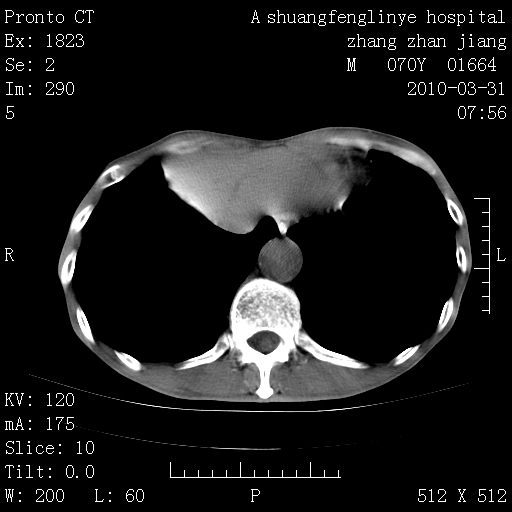

双上肺继发型tb并左上空洞形成,主动脉冠脉钙化。

支持:继发性肺结核伴空洞形成!建议纤支镜检查待出外周围型肺癌可能!

1)两肺上叶继发性肺结核并左肺上叶空洞形成。2)冠状动脉及主动脉钙化。